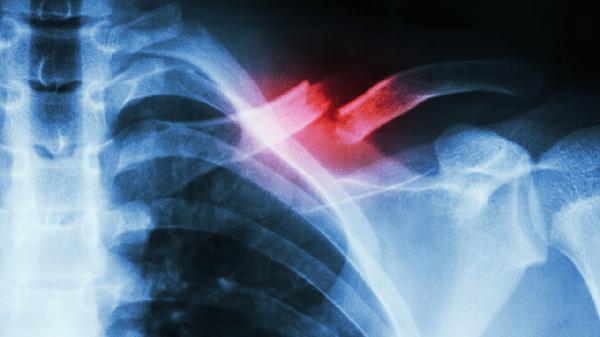

4、外伤:筛窦区域的直接外伤或手术操作可能刺激骨组织修复过程中出现异常增生。避免局部外伤,若因外伤导致骨瘤,需根据具体情况决定是否手术切除。